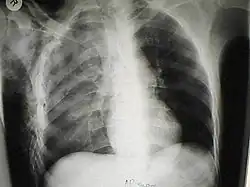

Diagnosis

Significant cases of subcutaneous emphysema are easy to diagnose because of the characteristic signs of the condition.[1] In some cases, the signs are subtle, making diagnosis more difficult.[13] Medical imaging is used to diagnose the condition or confirm a diagnosis made using clinical signs. On a chest radiograph, subcutaneous emphysema may be seen as radiolucent striations in the pattern expected from the pectoralis major muscle group. Air in the subcutaneous tissues may interfere with radiography of the chest, potentially obscuring serious conditions such as pneumothorax.[18] It can also reduce the effectiveness of chest ultrasound.[28] On the other hand, since subcutaneous emphysema may become apparent in chest X-rays before a pneumothorax does, its presence may be used to infer that of the latter injury.[13] Subcutaneous emphysema can also be seen in CT scans, with the air pockets appearing as dark areas. CT scanning is so sensitive that it commonly makes it possible to find the exact spot from which air is entering the soft tissues.[13] In 1944, M.T. Macklin and C.C. Macklin published further insights into the pathophysiology of spontaneous Macklin's Syndrome occurring as a result of a severe asthmatic attack.